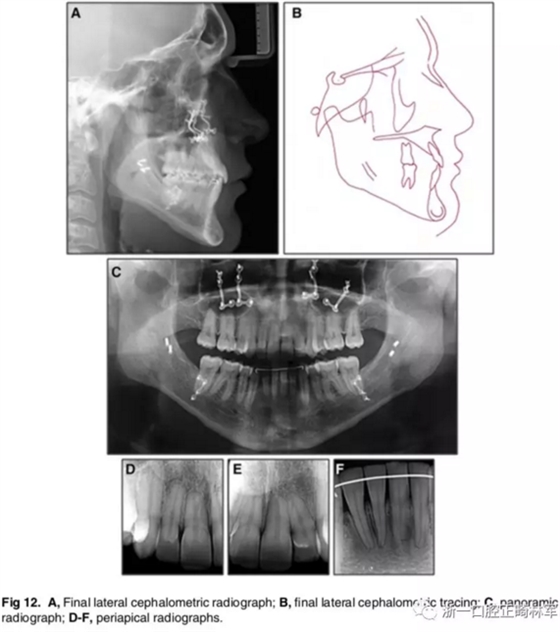

影像學(xué):全景片示:牙根平行度可。頭顱側(cè)位片及疊加圖示:顯著的骨性、牙性改變;其中,最大的改變?yōu)樯舷骂M位置關(guān)系,改變了7mm;由此帶來(lái)的改變?yōu)锳NB角從-4°變?yōu)?°,Wits值由-10mm變?yōu)?1.5mm,上頜突度減小(A-NPer,3mm),上下頜不調(diào)改善(Co-A-Co-Gn,41mm),從而使側(cè)貌更為平直;下頜磨牙遠(yuǎn)中移動(dòng),無(wú)伸長(zhǎng)、傾斜,反映了下頜整體的遠(yuǎn)中移動(dòng);上下切牙傾角糾正(1:NA,7mm、25°; 1:NB,4.5mm、20°; IMPA,78°),從而改善了在基骨中的位置。

功能:前伸合的切牙引導(dǎo)與側(cè)方合的尖牙引導(dǎo)得以實(shí)現(xiàn)。

側(cè)貌:上唇突度增大4mm(至S線0mm),整體側(cè)貌更為和諧。

5年隨訪:治療結(jié)果保持穩(wěn)定,無(wú)明顯復(fù)發(fā),但下頜中線有輕微偏移;下頜磨牙位置始終保持穩(wěn)定。